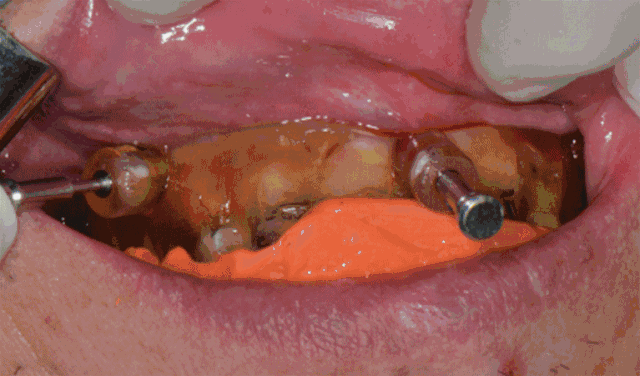

精彩案例: